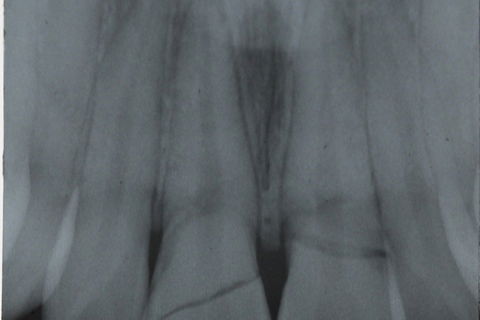

Paciente E.O.L chegou ao consultório sob queixa principal, um trauma sofrido por queda de motocicleta. Como mostra na FIGURA 1.  Na consulta foi feito uma avaliação clínica e tomada de uma radiográfia periapical como mostra na FIGURA 2.

Segunda a classificaçāo de fratura dentaria e suas caracterista clínica. foi constatado um fratura corono-radicula no elemento 21 ( envolvendo esmalte, dentina, polpa e fratura radicular na região do terço medio) e fratura de coronaria (envolveno esmalte, dentina e polpa) no elemento 11.